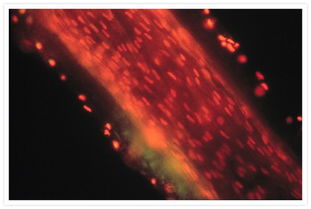

随着医学技术的不断发展,对inferior mesenteric artery的研究也在不断深入,近年来,研究人员利用影像学技术,如CT血管造影、MRI等,对inferior mesenteric artery的解剖结构和生理功能进行了更加详细的研究,这些研究有助于医生更准确地诊断和治疗肠道疾病,提高了患者的治疗效果和生存质量。

还有一些研究人员关注inferior mesenteric artery在药物研发和基因治疗等领域的应用,通过研究inferior mesenteric artery的生理功能和药物作用机制,可以为新药的开发提供依据,基因治疗等技术也可以为inferior mesenteric动脉疾病的治疗提供新的思路和方法。